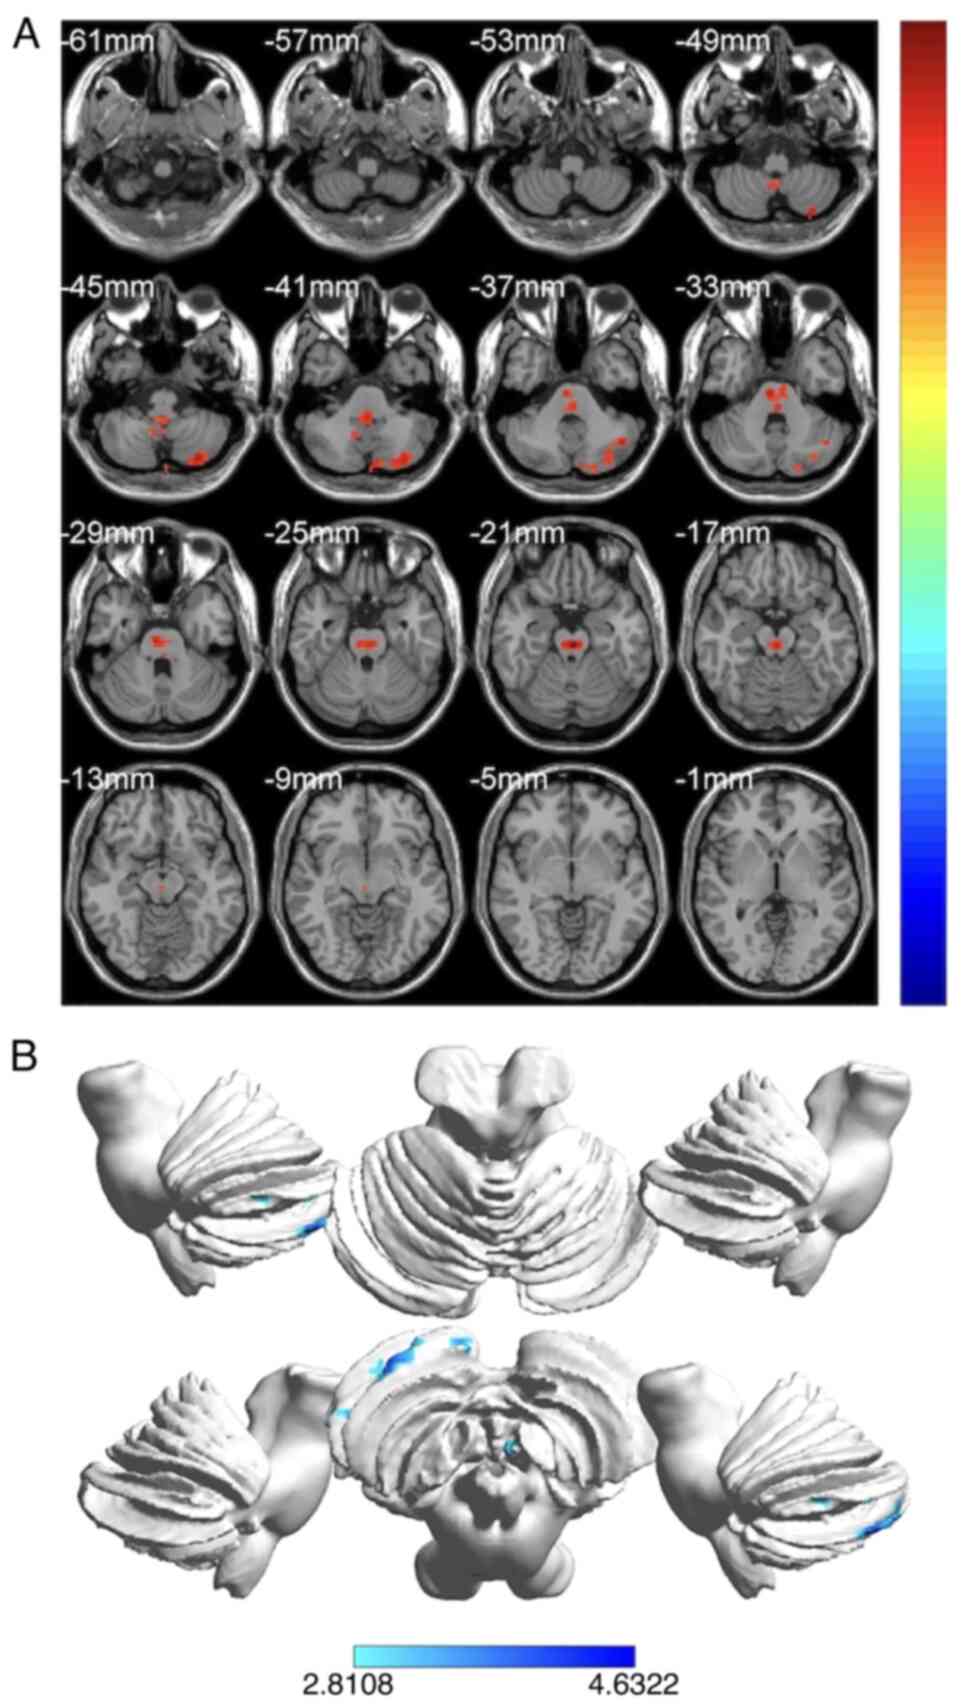

The present study aimed to investigate potential functional network brain‑activity abnormalities in individuals with orbital fracture (OF) using the voxel‑wise degree centrality (DC) technique. The present study included 20 patients with OF (12 males and 8 females) and 20 healthy controls (HC; 12 males and 8 females), who were matched for gender, age and educational attainment. Functional magnetic resonance imaging (fMRI) in the resting state has been widely applied in several fields. Receiver operating characteristic (ROC) curves were calculated to distinguish between patients with OF and HCs. In addition, correlation analyses were performed between behavioral performance and average DC values in various locations. The DC technique was used to assess unprompted brain activity. Right cerebellum 9 region (Cerebelum_9_R) and left cerebellar peduncle 2 area (Cerebelum_Crus2_L) DC values of patients with OF were increased compared with those in HCs. Cerebelum_9_R and Cerebelum_Crus2_L had area under the ROC curve values of 0.983 and 1.000, respectively. Patients with OF appear to have several brain regions that exhibited aberrant brain network characteristics, which raises the possibility of neuropathic causes and offers novel therapeutic options.